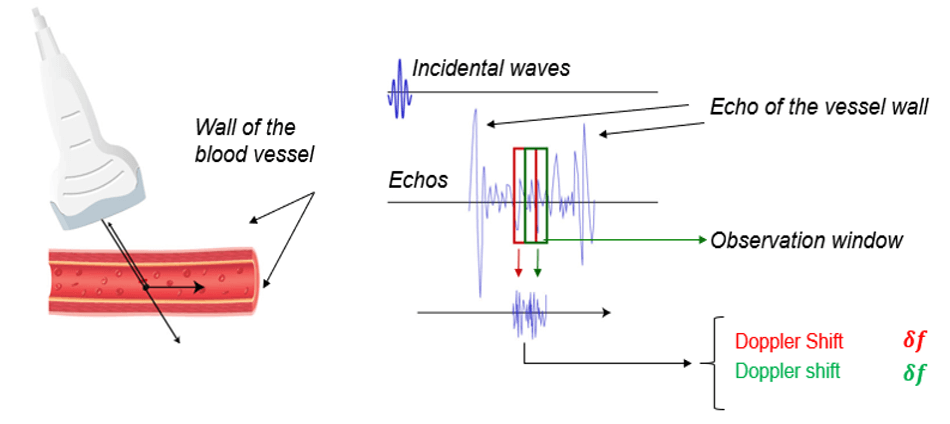

Pulsed Doppler

In general, Doppler ultrasound and obstetric ultrasound scanners use pulsed wave ultrasound. This allows the measurement of the depth of the flow site. In pulsed Doppler systems, an ultrasonic sensor emits a brief pulse at a regular time interval, then goes into receive mode immediately after each transmission.

An observation window called the “Doppler window” selects the echoes scattered by the red blood cells moving at a given depth. The velocity of the red blood cells is measured at a specific depth that can be adjusted.

Unfortunately, the pulsed Doppler system presents many disadvantages. First, this system is unable to measure high velocities. Second, pulsed wave systems suffer from a fundamental limitation, which is the aliasing artifact.